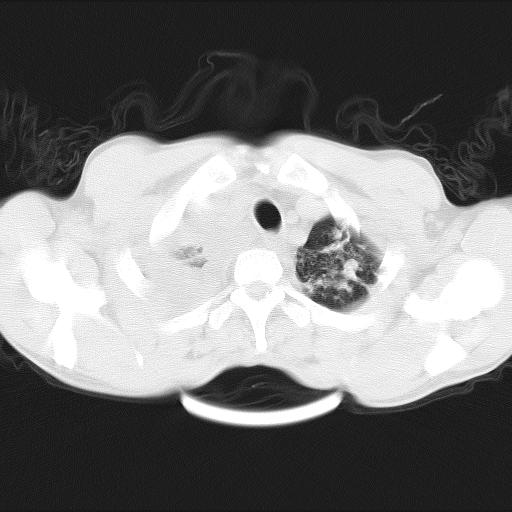

男性,44岁,结核病史多年。现胸闷气短,咳嗽,偶咳血。

右侧胸腔积液

右肺下叶不张

双肺多发结节影最分空洞形成考虑占位不除外结核

1、右侧大量胸腔积液伴右肺压缩性膨胀不全,建议抽液治疗后复查 2、两肺继发性tb伴空洞形成。

1)两肺继发性肺结核伴空洞形成,左肺多发性结核球。2)右侧大量胸腔积液伴右肺部分膨胀不全。3)纵隔淋巴结肿大。